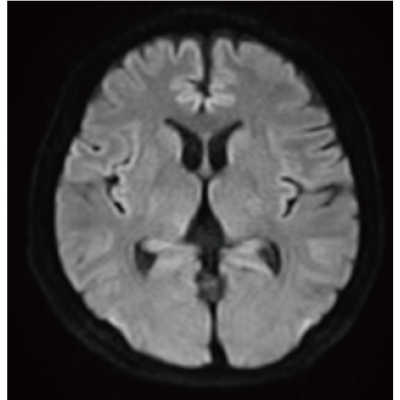

IP-RAPID x DLR Plus can be used for basic imaging such as VolumeScan, RadialScan, HalfScan, and many other imaging methods such as MultiContrastScan FatSep and DWI.

It can also be used with time-consuming scans such as Whole Body DWI and Whole Spine imaging, providing more detailed information in many areas than previously possible.

Deep Learning technology*8 enables image quality adjustment after imaging is complete. It optimize SNR and improve image sharpness by processing MRI signals in stages (k-space signal processing).

This brings super-resolution and reduces truncation artifacts.